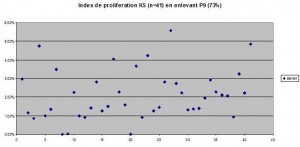

Methods: We took after approval of the ethics committee 36 seborrheic keratosis and 15 specimens of control skin (plastic surgery, inflammatory skin (biopsies of suggested lymphomas with ki.67 analysis but with no epidermotropism or atypical cells) which were sent for histological analysis and ki-67 marking (method in detail). Two groups within the SK group were done: all histologies compatible with a reticulate SK or acanthotic SK were put in the RA (reticuloacanthotic group) and the hyperkeratotic SK were put in the AHCS group. There were no clonal specimens. We did not take into account the pigmentation of cells, nor their degree of irritation. The keratinocytes in SK and control skin was then done. All ki-67* fully positive cells and a fine estimate of the number of cells was done under a microscope lens of 40x magnification. An average of four adjacent fields was done. Then a ki-67 proportion index for control skin and SK was done by dividing the total number of cells.

Results: The proportion of Ki-67 positive cells out of all SKS altogether equalled 2.3% +/- 0.3% whereas the one of control skin was 8.27% +/- 0.7%. One of the specimens was subtracted from the study because the proportion of ki-67 positive cells equalled 72%!There was no statistical difference between the two chosen histological types of SK( reticulo-acanthotic 2.0 +/- 0.5% versus acanthohyperkeratotic 2.6% +/- 0.3%. The difference was statistically significant between SK and the control group. The control group divided into two groups, one on inflamed skin and the other on normal skin showed a statistical difference with the inflammatory group showing a bigger percentage of ki-67 positive cells.

Proportion of ki-67 positive cells. The values equal to 0% (All Acanthohyperkeratotic) were taken into account. Even if these values were not taken into account, the difference between normal skin and acanthohyperkeratotic and SK as a whole would not be significantly changed, as the standard deviation would be decreased.

Methods: We took after approval of the ethics committee 36 seborrheic keratosis and 15 specimens of control skin (plastic surgery, inflammatory skin (biopsies of suggested lymphomas with ki.67 analysis but with no epidermotropism or atypical cells) which were sent for histological analysis and ki-67 marking (method in detail). Two groups within the SK group were done: all histologies compatible with a reticulate SK or acanthotic SK were put in the RA (reticuloacanthotic group) and the hyperkeratotic SK were put in the AHCS group. There were no clonal specimens. We did not take into account the pigmentation of cells, nor their degree of irritation. The keratinocytes in SK and control skin was then done. All ki-67* fully positive cells and a fine estimate of the number of cells was done under a microscope lens of 40x magnification. An average of four adjacent fields was done. Then a ki-67 proportion index for control skin and SK was done by dividing the total number of cells.

Results: The proportion of Ki-67 positive cells out of all SKS altogether equalled 2.3% +/- 0.3% whereas the one of control skin was 8.27% +/- 0.7%. One of the specimens was subtracted from the study because the proportion of ki-67 positive cells equalled 72%!There was no statistical difference between the two chosen histological types of SK( reticulo-acanthotic 2.0 +/- 0.5% versus acanthohyperkeratotic 2.6% +/- 0.3%. The difference was statistically significant between SK and the control group. The control group divided into two groups, one on inflamed skin and the other on normal skin showed a statistical difference with the inflammatory group showing a bigger percentage of ki-67 positive cells.

Proportion of ki-67 positive cells. The values equal to 0% (All Acanthohyperkeratotic) were taken into account. Even if these values were not taken into account, the difference between normal skin and acanthohyperkeratotic and SK as a whole would not be significantly changed, as the standard deviation would be decreased.